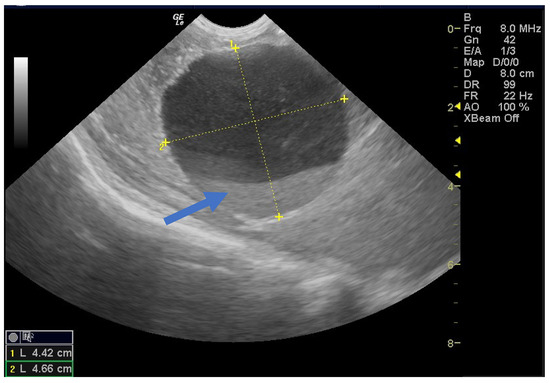

One hemorrhagic-looking cyst remained unchanged after two months but resolved completely after 8 months, and no follow-up evaluation information was available for another case (Figure 7).

Figure 7.

Ultrasound image of a simple cyst showing a blood clot (arrow) that resolved spontaneously after 8 months postpartum.